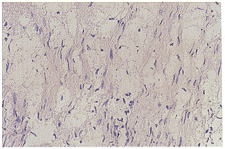

A组:移植3周组神经纤维变粗,大小不一,髓鞘肿胀及空泡变性如泡沫状,神经轴索崩解 、断裂,神经内膜管连续性好。神经束膜、神经内膜和神经外膜均有较多单核细胞、淋巴细 胞浸润,神经内膜和神经束膜有大量新生毛细血管,内皮细胞肿胀。移植8周组神经纤维仍 有水肿,可见稀疏再生轴束出现。移植12周组神经纤维肿胀及淋巴细胞、单核细胞浸润较 前两组减轻,雪旺细胞增生明显,轴索数量较前增加。16周组又较12周组有好转,大量 再生轴索出现,接近正常神经纤维密度,淋巴细胞、单核细胞集中在移植神经远端和神经束 膜及神经外膜(图1见封三)。

图1 A组神经移植后16周,大理再生轴索和雪旺细胞出现,接近正常神经密度,仍可见少量炎细胞浸润。HE×400